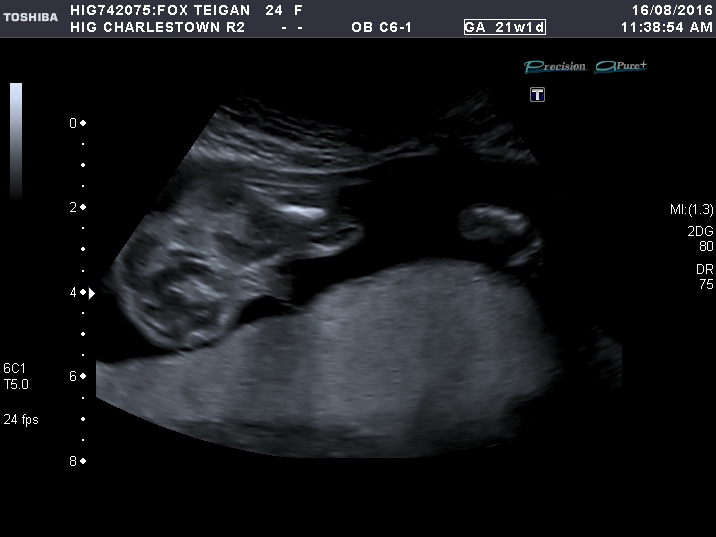

21 week scan :)

Attachment 32704

Sorry forgot to mention the more I look at the 21 weeks I think maybe its the cord? they had there legs shut for most of the scan to the very last try at a peak what's inbetween.